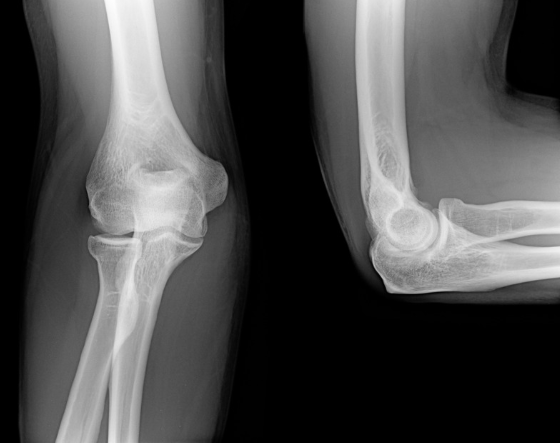

上記の保存治療でも改善ない場合は、手術をお勧めします。手術は図の緑の神経の通り道が狭くなっている部分を切開し圧迫をとる手術です。その際は近隣の手術ができる整形外科病院へ紹介いたします。